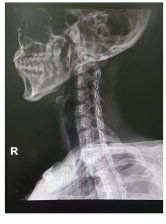

목디스크 증상 원인 치료방법 총 정리 알아봐요 목디스크 증상 원인 치료방법 등 목 디스크 관련 정보에 대해 알아보도록 하겠습니다. 목디스크는 인간의 척추 중 경추부나 흉추부에 위치한 디스크(틀니)가 변형되어 생긴 질환으로, 경추부의 경우 목의 통증, 저림 혹은 근육 경련, 어깨와 팔의 통증, 감각상실 등이 나타나며, 흉추부의 경우 흉부의 통증, 등의 통증 등이 나타납니다. 보통은 원인불명성으로 인한 자연적인 회복을 기다리는 것이 가장 좋으며, 통증이 심한 경우 보조적으로 항통제나 근육 이완제 등을 사용합니다. 만약 압력이 심한 경우 수술이 필요할 수 있습니다.예방법으로는 바른 자세 유지와 체중 조절, 충분한 운동, 목과 등의 근육 강화 등이 있습니다.

목 디스크는 경추부나 흉추부의 디스크(틀니) 변형으로 인해 발생하는 질환으로, 다음과 같은 증상이 나타날 수 있습니다.

목 디스크 원인

목 디스크는 디스크(틀니)가 변형되어 생기는 질환으로, 다음과 같은 원인이 있을 수 있습니다.